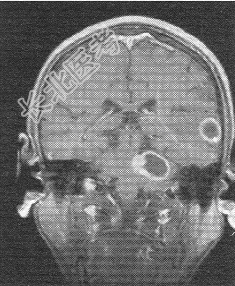

- 单项选择题患者男,72岁。肺癌术后一年余, 现出现头晕头痛,MR图像如下, 最具有可能的诊断是

B、脑转移癌